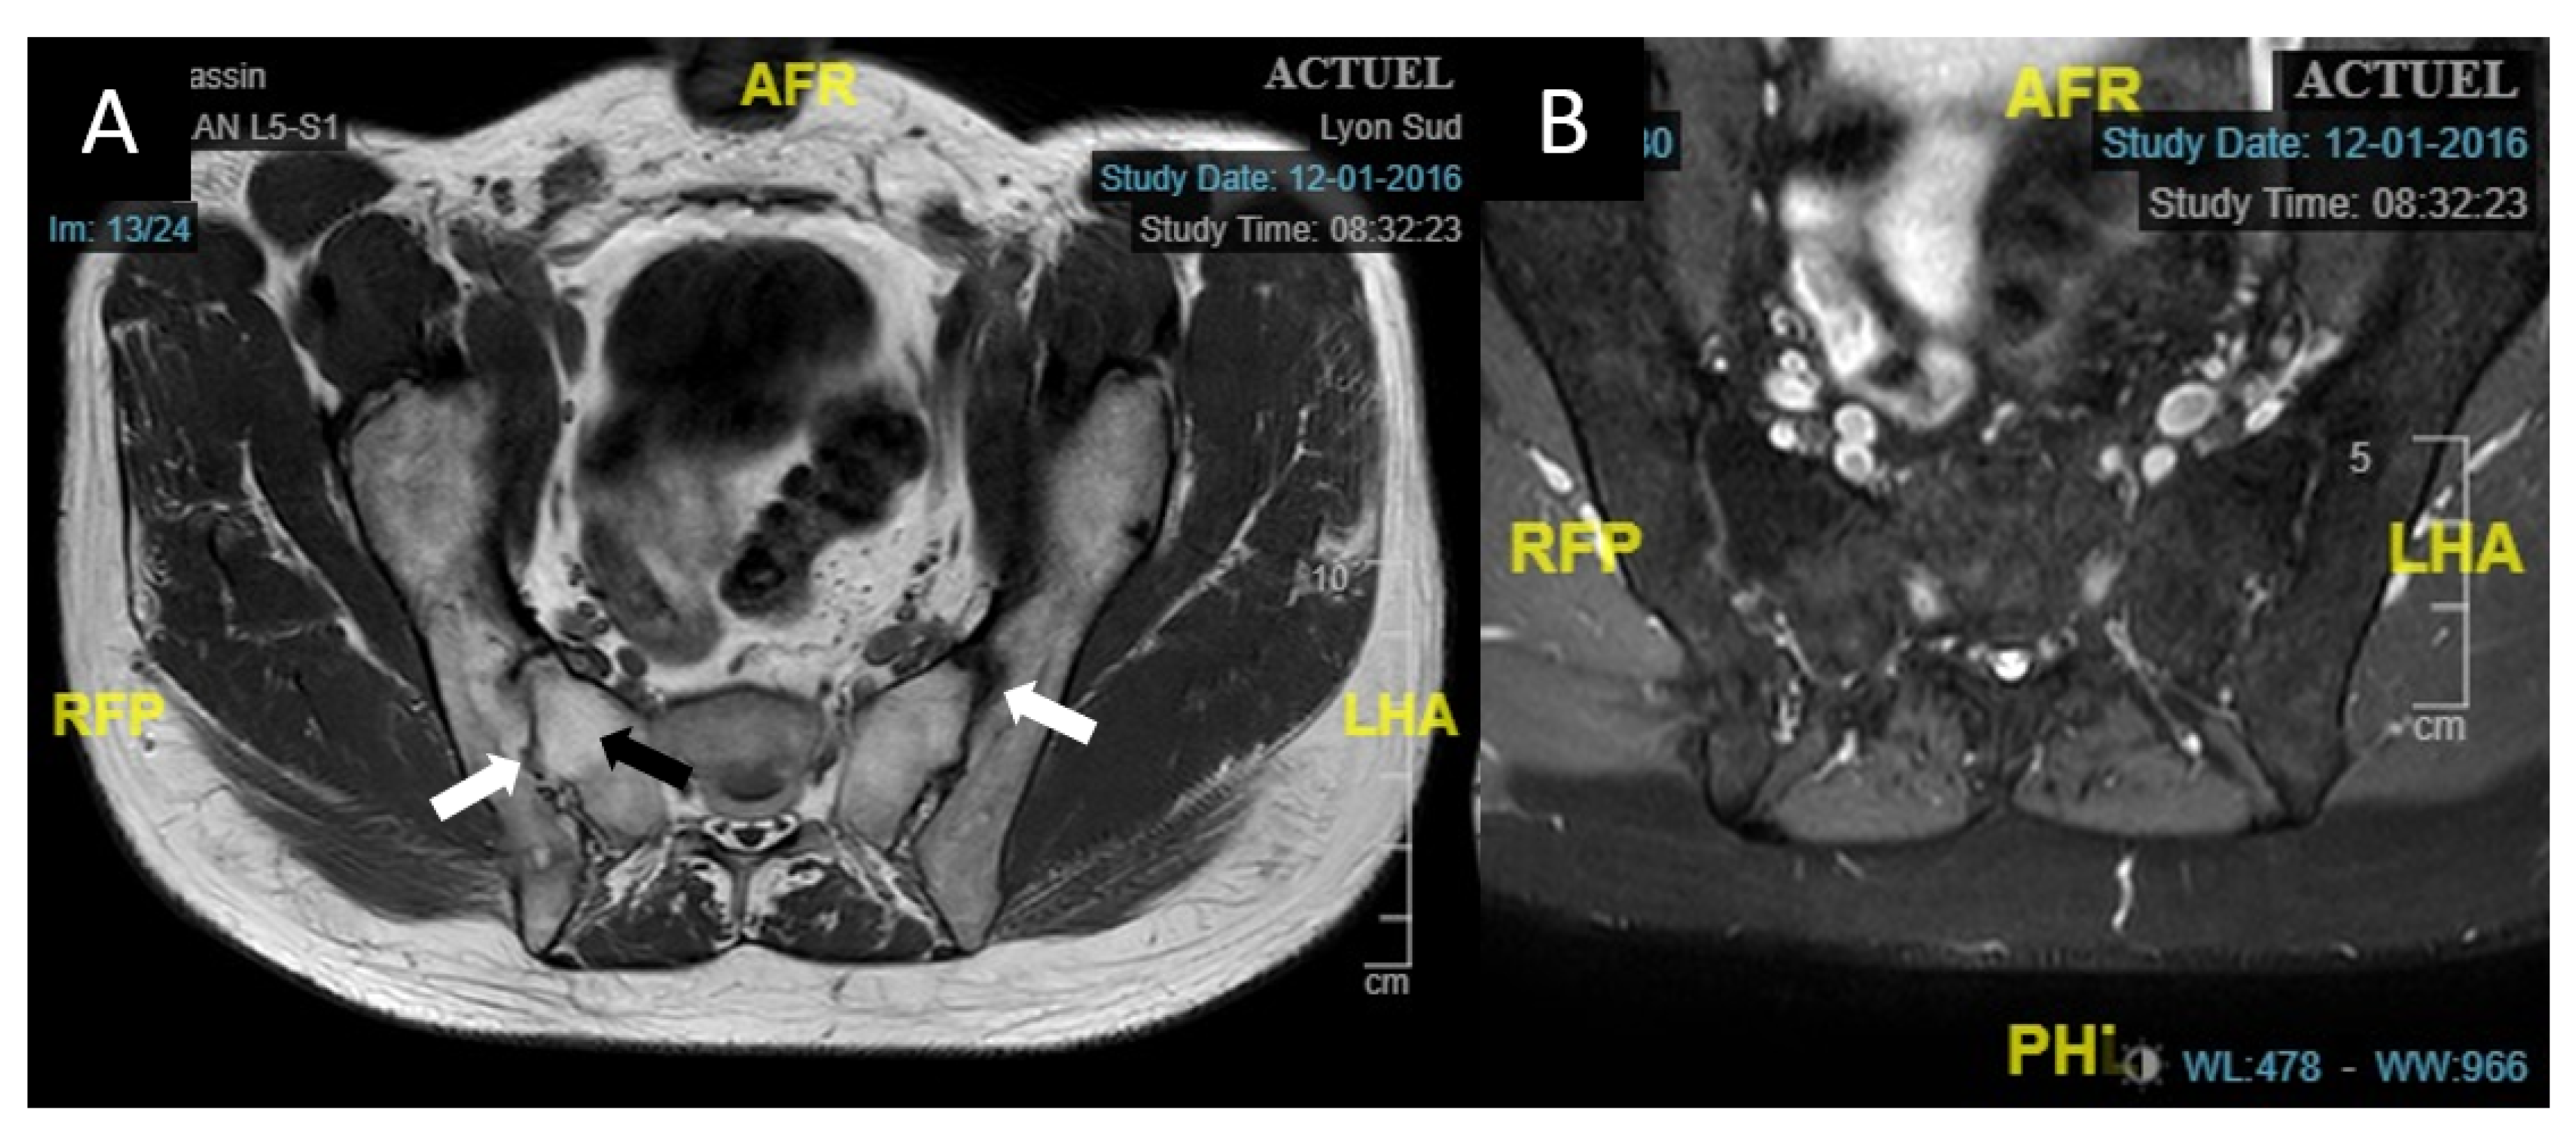

Laboratory testing found normal complete blood count (CBC), C-reactive protein (CRP) at 6.5 mg/L, and negative Syphilis serology. Chest X-ray was normal. HLA testing revealed the presence of the HLA-B27 haplotype. Magnetic Resonance Imaging (MRI) of sacroiliac joints found signs of ankylosis in the right side, and major fatty restructuring on both sides, as well as discrete condensation in the anterior part of the articulation, reflecting a history of inflammatory rheumatism. There was no edema in favor of active sacroiliitis (Figure 2). The diagnosis of Spa was established, with a basal activity BASDAI score of 3.5. Treatment for the acute AU included topical steroids with slow tapering, and systemic treatment with sulfasalazine (SSZ) was initiated to decrease the frequency and duration of relapses. AU regressed over the first month and there was only one episode of relapse during the next three years.